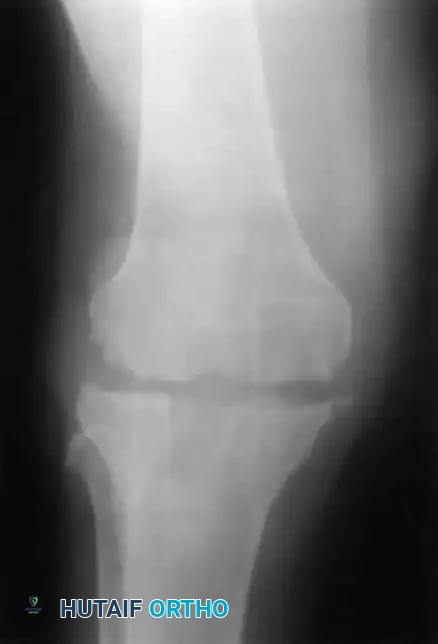

Standard AP radiograph of a well-fixed TKA. Baseline imaging is critical for future comparison.